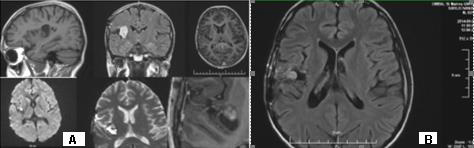

A 17-year-old boy with extremely rare primary brain neuroblastoma/supratentorial primitive neuroectodermal tumor (PNET) in the right temporo-parietal region is presented. Complex treatment, including subtotal surgery, conventional fractionated craniospinal radiotherapy (CSRT) with DD 1.8 Gy up to TD 30 Gy with boost RT in the tumor bed up to TD 56 Gy with DD 1.8 Gy and 6 courses of adjuvant Ch (Etoposide and Carboplatin) was conducted (Figure 10). After 2 years of control MRI, a local recurrence was established (Figure 11), in which an additional local RT with DD 2Gy to TD 34Gy was performed. After 7 months of complementary local RT, MRI demonstrated local tumor control (Figure 12). After three months of MRI, a second local recurrence was diagnosed, which was operated on (Figure 13/А). Postoperative bone marrow transplantation of stem cells was performed, but 1 year later a third local recurrence was diagnosed (Figure 13/В).

The third recurrence was operated. Histological result: Brain tissue with infiltration from nests and derived from small atypical cells with hyperchromic nuclei and visible nucleoli. Tumor cells form pseudosockets. Focal hemorrhages and necrosis are seen- Histological data for neuroblastoma. Given the previous peripheral stem cell transplantation and the high risk of hematological toxicity, 6 courses of Ch with Vincristine and Temodal in a reduced dose were administrated. MRI 2 months after the completion of Ch visualized a fourth local recurrence and the patient was referred to radiosurgery with a gamma knife in Turkey where a single TD 14 Gy has been performed. Paresis of the left limbs suddenly occurred 2 months after the procedure. On contrast-enhanced MRI with evidence of subacute hematoma in the postoperative porencephalic cyst in the right temporoparietal brain area (Figure 14/А). СT in 20 days reported a persistent subacute hematoma in the right temporoparietal postoperative porencephalic cyst (Figure 14/ B).

Figure 10: MRI of primary brain neuroblastoma: A / Preoperative; C / Postoperative; C / Local tumor control after complex treatment / subtotal surgery, CSRT with boost RT in the tumor bed up to 56 Gy and 6 cycles of chemotherapy according to the BEP protocol.

In the fourth clinical case, the young boy with the rare diagnosis of brain neuroblastoma (PNET) concerns extremely malignant neoplasm. Complex treatment, including subtotal surgery, conventional fractionated craniospinal radiotherapy (CSRT) with DD 1.8 Gy up to TD 30 Gy with boost RT in the tumor bed up to TD 56 Gy with DD 1.8 Gy and 6 courses of adjuvant Ch (Etoposide and Carboplatin) was applied (Figure 10). After 2 years of control MRI, a local recurrence was established (Figure 11), in which an additional local RT with DD 2Gy to TD 34Gy was performed. The prognosis and survival directly depend on the volume of the surgery, the magnitude of the postoperative brain residue (>1.5 cm2), the infiltration of the IV ventricle and the pathohistological cell variant [69,70]. Subtotal surgical resection and evidence of disease dissemination are considered poor prognostic factors [71]. In adult patients, the five-year progression-free survival rate ranges from 45% to 78% depending on the risk class [72-74]. In the young patient with a primary brain PNET, the bone marrow transplantation with stem cells was conducted, 1 year after which we diagnosed third local recurrence (Figure 13). For a period of 5 years, despite complex treatment, including subtotal surgery, conventional fractionated CSRT with boost, Ch, local RT and bone marrow transplantation, 2 months after the completion of Ch on MRI, a fourth local recurrence occurred, subjected to radiosurgery with a gamma knife in Turkey with a single fraction 14 Gy. After 2 months from SRS, contrast-enhanced MRT reported evidence of late subacute hematoma in the postoperative porencephalic cyst in the right temporoparietal brain area (Figure 14/А). СT in 20 days reported a persistent subacute hematoma in the right temporoparietal postoperative porencephalic cyst (Figure 14/B).